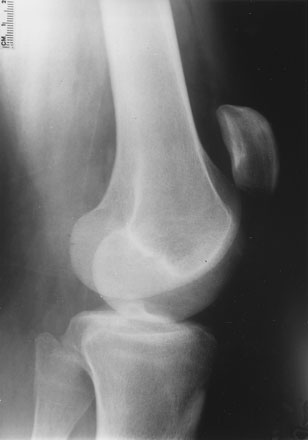

Radiographs

• Patella alta

When the patella rides high on the lateral view of a radiograph (as seen in the above figure) it is called patella alta and a ratio establishes the extent of displacement. Patella alta occurs when the patellar tendon ruptures.